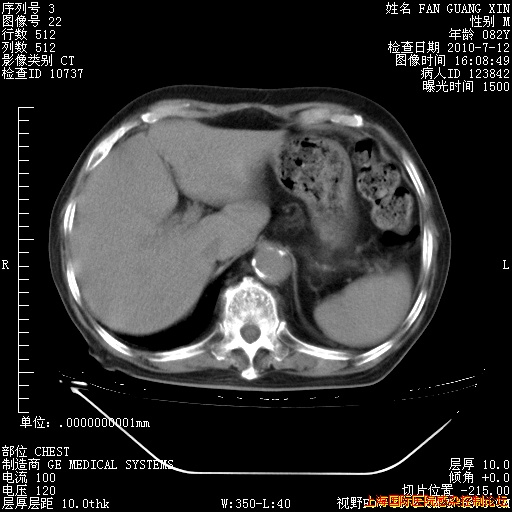

今天复查CT

今天CT

整整相隔30天的肺部CT好像有所好转啊。甲强龙减量第3天,需要观察体温。

海管,自昨日你和我通完话后,不知您岳父消化道症状有无缓解?体温怎样?阅读7.12日胸部ct,个人认为目前激素治疗是有效的,甲强龙减量是适宜的。因在抗痨治疗,需密切观察肝功、肾功能和血常规。不过,老年、长期住院和大量使用激素,很担心菌群失调发生